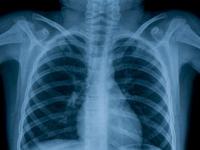

Esta es la enfermedad más peligrosa del mundo según la OMS Viernes, Septiembre 21, 2018 - 13:48La tuberculosis sigue siendo la enfermedad infecciosa más mortal del mundo.Leer más